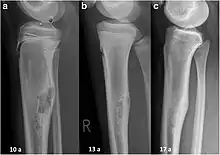

Non-ossifying fibroma of tibia

The most common bone tumor is a non-ossifying fibroma.[4] Average five-year survival in the United States after being diagnosed with bone and joint cancer is 67%.[5] The earliest known bone tumor was an osteosarcoma in a foot bone discovered in South Africa, between 1.6 and 1.8 million years ago.[6]

An arm bone tumor